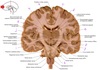

37

a

body of fornix

38

b

Septum pellucidum

39

c

Body of corpus callosum

40

d

Body of lateral ventricle

41

e

Body of caudate nucleus

42

f

Posterior limb of internal capsule

43

g

Putamen

44

h

Tail of caudate nucleus

45

i

Interpeduncular fossa

46

j

interthalamic adhesion

47

k

Inferior horn of lateral ventricle

48

L

Hypothalamus

49

m

Corona radiata